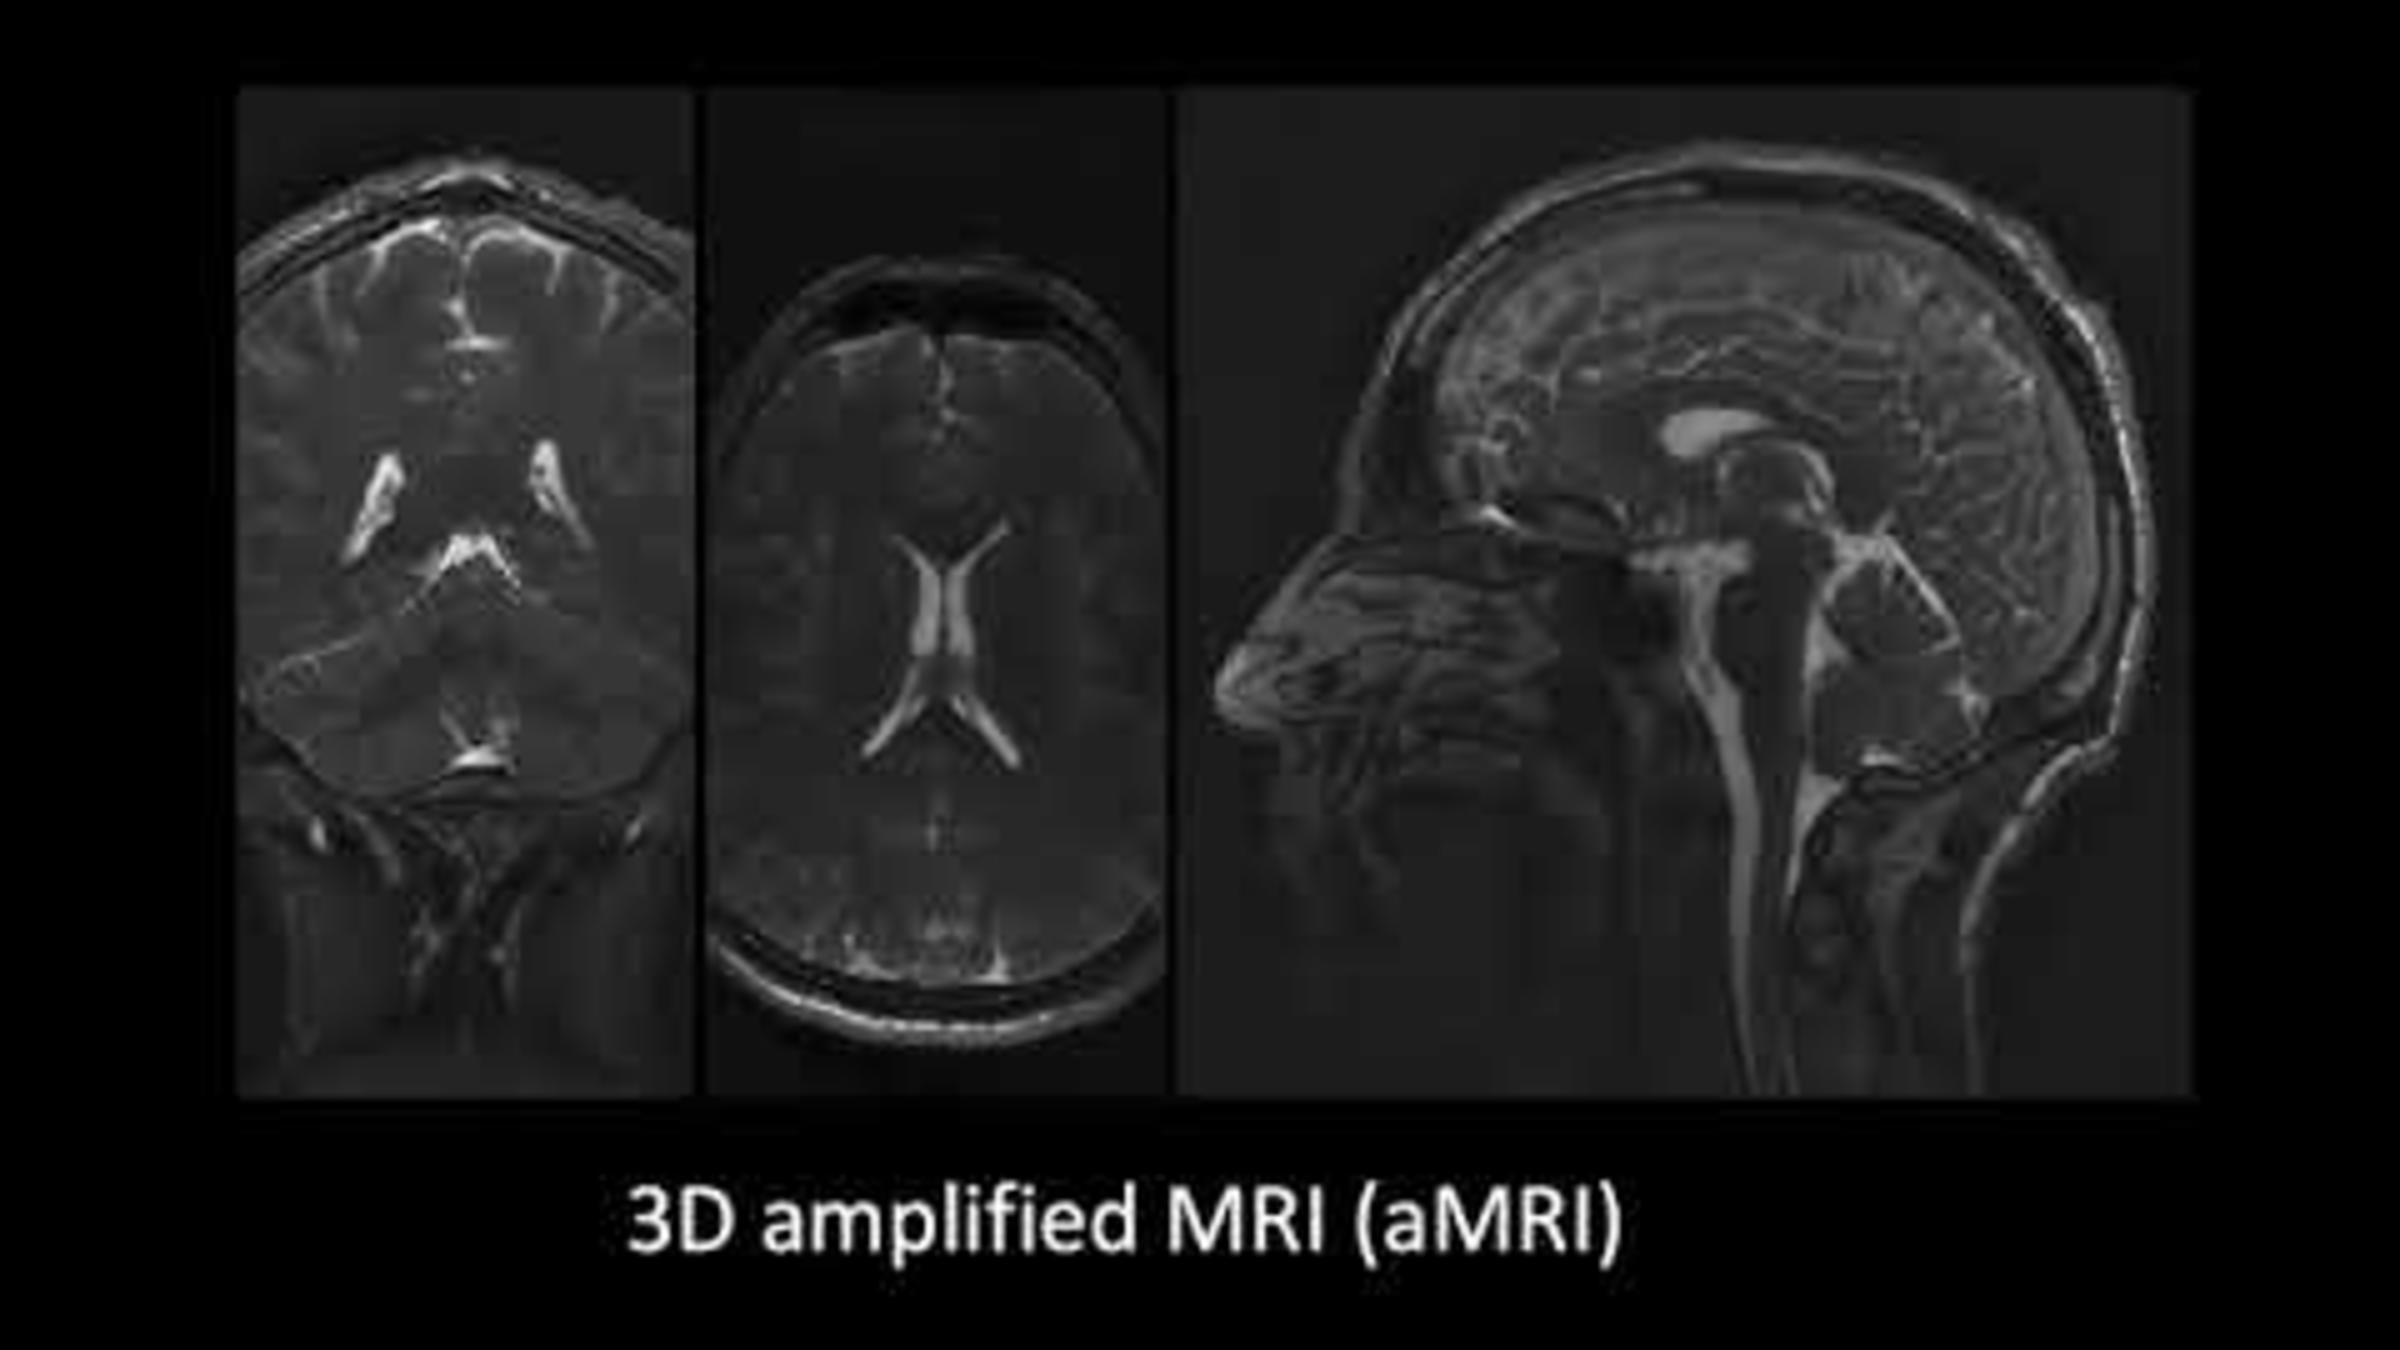

Using the new 3D aMRI software, 4D animation models of brain motion can be created from an MRI image. The striking detail of these animated magnified movements may be able to help identify abnormalities, such as those caused by blockages of spinal fluids, which include blood and CSF (spinal fluid in the brain). 3D aMRI method outlined in Terem et al. Magnetic Resonance in Medicine (2021); Abderezaei et al. Brain Multi-physics (2021). https://youtu.be/mRsnPqK4LCQ

3D aMRI of the human brain shows minute movements of the brain at an unprecedented spatial resolution of 1.2mm3, approximately the width of a human hair. The actual movements are amplified (made larger, up to 25 times) to allow clinicians and researchers to view the movements in detail. The striking detail of these animated magnified movements may be able to help identify abnormalities, such as those caused by blockages of spinal fluids, which include blood and cerebrospinal fluid.